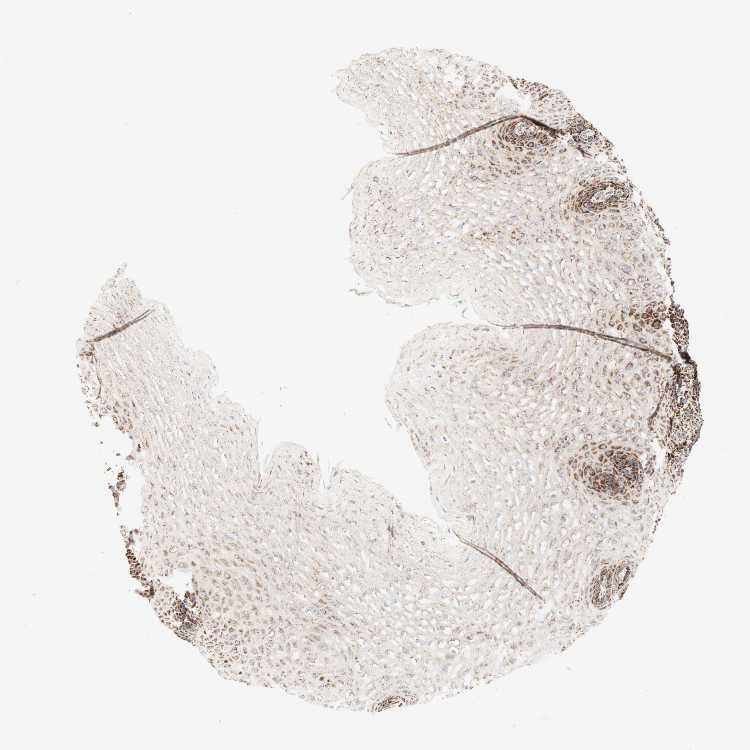

ESOPHAGUS - Antibody stainingi

Antibody staining in the annotated cell types in the current human tissue is reported as not detected, low, medium, or high, based on conventional immunohistochemistry profiling in selected tissues. This score is based on the combination of the staining intensity and fraction of stained cells.

Each image is clickable and will lead to virtual microscopy that enables deeper exploration of all samples and also displays staining intensity scores, fraction scores and subcellular localization as well as patient and tissue information for each sample.

Antibody HPA011562Antibody CAB005585

Squamous epithelial cells HighHigh